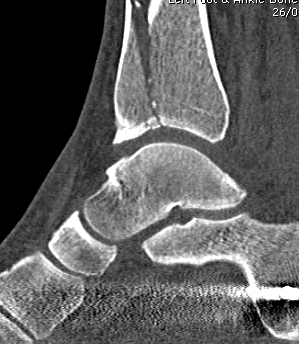

CT scan

Commonly 3 fracture configurations

- medial malleolus

- posterolateral fragment / Volkmann

- anterolateral fragment / Chaput